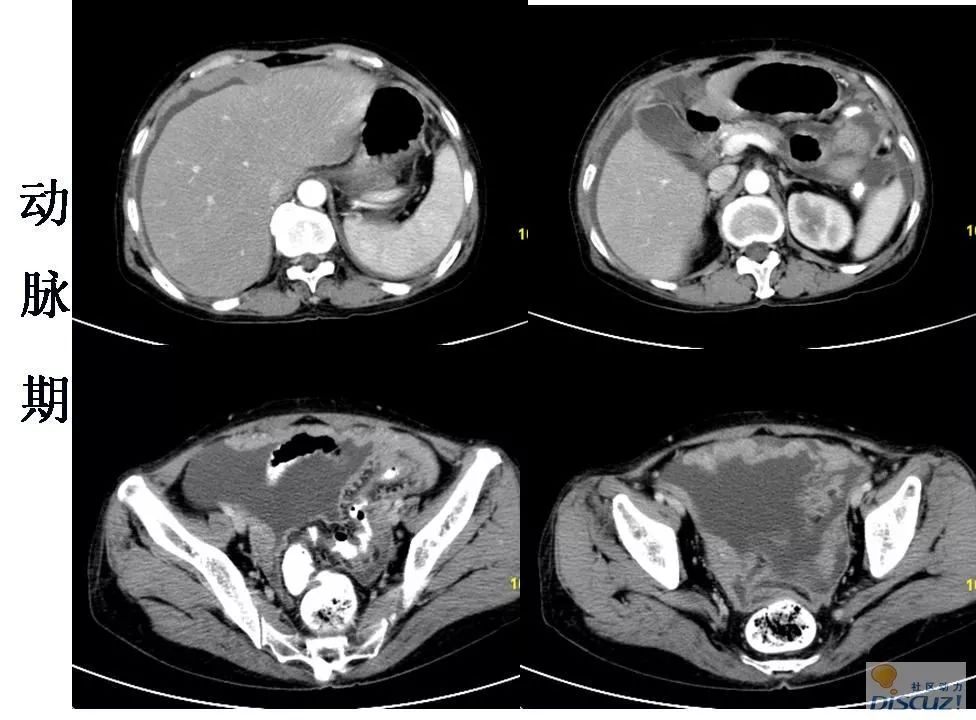

病例分享:晚期卵巢癌介入治疗

图片尺寸750x562